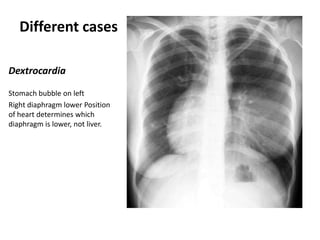

Dextrocardia

Stomach bubble on left

Right diaphragm lower Position

of heart determines which

diaphragm is lower, not liver.